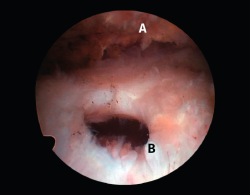

Figura 1. Rotura en forma creciente. A: acromion; B: rotura en forma de semiluna del tendón supraespinoso.

Figura 5. Rotura de tipo C1. A: rotura pequeña de espesor completo del supraespinoso; B: cabeza humeral.

Sin embargo, las clasificaciones basadas en el tamaño de la rotura deben ser bidimensionales, ya que la visión unidimensional puede ser engañosa, al mostrar el tamaño de la rotura solo desde el plano anteroposterior(4). Por esta razón, proponemos el sistema de clasificación del manguito posterosuperior sugerida por Snyder, que aporta información no solo del tamaño, sino del número de tendones afectados y la presencia de tejido cicatricial(7). En las lesiones de tipo C1 la lesión atraviesa todo el espesor del tendón y en el eje transversal es pequeña y punzante (Figura 5). Las de tipo C2 son roturas de espesor completo pero la distancia entre los extremos de la rotura es menor de 2 cm con escasa retracción (Figura 6). En las de tipo C3 la rotura afecta en sentido transversal entre 3 y 4 cm con mayor retracción implicando 2 tendones (Figura 7). Y las de tipo C4 son la rotura masiva del manguito de los rotadores con una afectación de espesor completo de toda la anchura de 2 o más tendones asociando importante retracción (Figura 8).